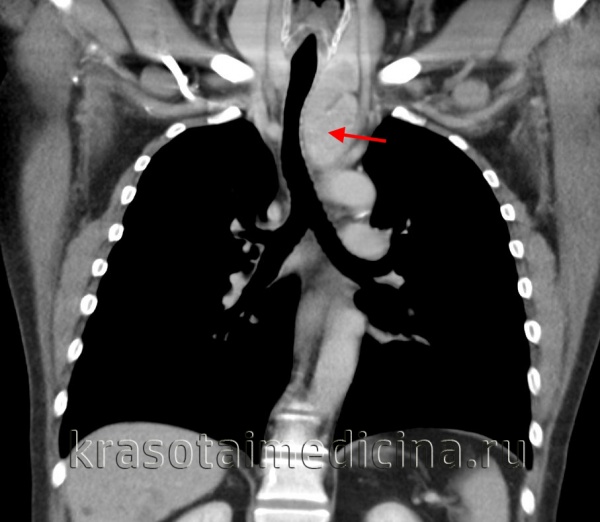

Компрессионный синдром

Компрессия венозных стволов, прежде всего, проявляется так называемым синдромом верхней полой вены (СВПВ), при котором нарушается отток венозной крови от головы и верхней половины туловища. Синдром ВПВ характеризуется тяжестью и шумом в голове, головной болью, болями в груди, одышкой, синюшностью и отечностью лица и грудной клетки, набуханием вен шеи, повышением центрального венозного давления. В случае сдавления трахеи и бронхов возникают кашель, одышка, стридорозное дыхание; возвратного гортанного нерва - дисфония; пищевода – дисфагия.